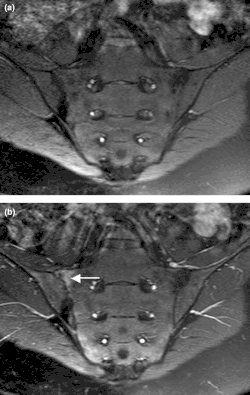

Magnetic resonance images of sacroiliac joints: psoriatic arthritis. Shown are T1-weighted semi-coronal magnetic resonance images through the sacroiliac joints (a) before and (b) after intravenous contrast injection. Enhancement is seen at the right sacroiliac joint (arrow), indicating active sacroiliitis.

Imaging is crucial to the spondyloarthritis diagnosis process. The most distinctive radiographic observation is the sacroiliac (SI) joints' erosion, ankylosis, and sclerosis.[27] There must be clear evidence of sacroiliitis (at least grade 2 bilaterally or grade 3 unilaterally) on the radiographs to diagnose ankylosing spondylitis. When axial spondyloarthritis is suspected, sacroiliac joint radiographs are still the initial imaging approach. If radiographs clearly show sacroiliitis, then no more diagnostic imaging is required. But because structural change seen on radiographs can take months or years to emerge, normal radiographs or worrisome abnormalities only warrant additional diagnostic imaging in the context of suggestive clinical symptoms or findings.[28] Furthermore, reading sacroiliac joint radiographs can be difficult and dependent on several variables, such as the image quality, the radiological technique, the reader's background, and variations in sacroiliac anatomy.[29][30]

A challenge associated with radiographic imaging is the typical ten-year lag between the beginning of inflammatory back pain and the development of radiographic sacroiliitis.[26] MRI imaging of the spine and entheses has made it possible to distinguish between inflammatory spinal lesions associated with ankylosing spondylitis and those unrelated to it earlier than is feasible with traditional radiography. It has also allowed for accurate anatomical description of spinal components.[31] The only imaging modality that can precisely identify and evaluate spinal inflammation at this time is magnetic resonance imaging (MRI) of the sacroiliac joints and spine. It is also being developed as a gauge of disease activity and response to treatment.[5]